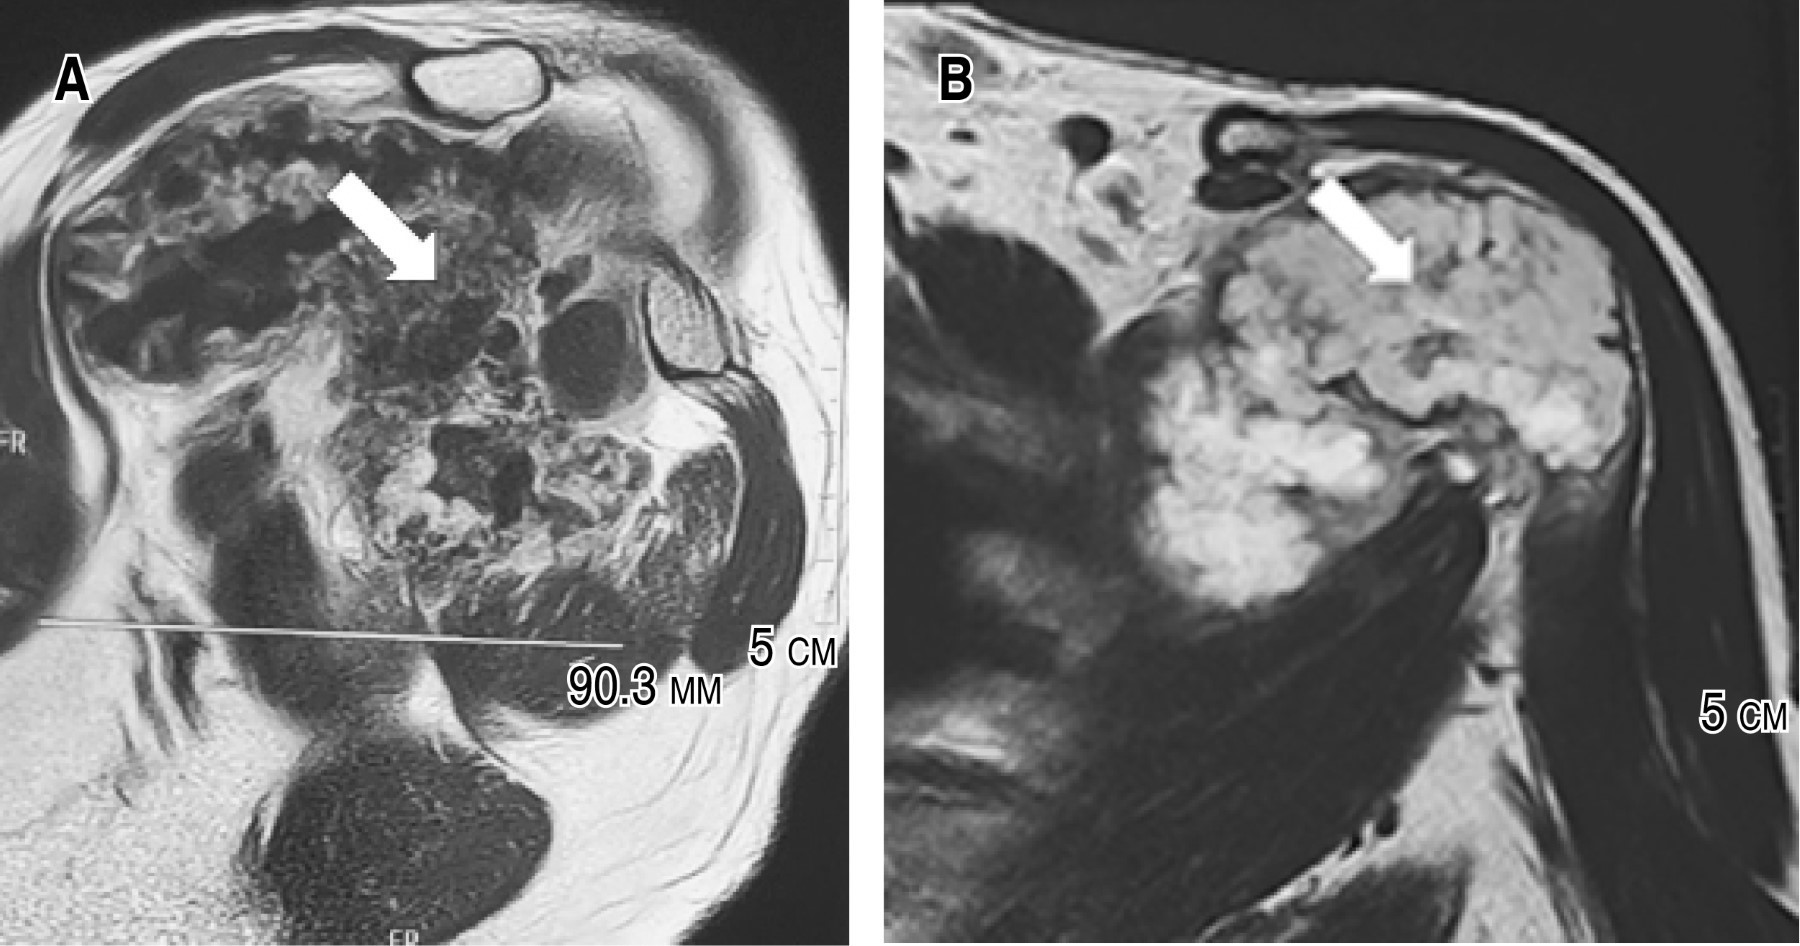

Se continuó el abordaje diagnóstico con una resonancia magnética (RMN) contrastada de hombro (Figura 2) que reportó una lesión quística encapsulada de 105 × 112 × 90.3 mm con hiperintensidad, lobulada y heterogénea, que comprime los músculos supraespinoso, deltoides y subescapular izquierdos.

El abordaje diagnóstico del condrosarcoma necesita el uso de estudios de imagen complementarios. Las directrices actuales recomiendan radiografías simples e imágenes transversales de todo el hueso afectado (RMN) para evaluar ubicación, extensión, actividad, naturaleza cartilaginosa e identificar metástasis omitidas.1,11 Radiográficamente se observan lesiones radiolucentes; los CS de alto grado de gran tamaño muestran apariencia apolillada, en el CS grado 2 se exhibe una tumoración mal definida, con leve mineralización de la matriz, aunado a destrucción ósea permeable.1,10,14 La RMN con o sin contraste es el estándar de oro en el diagnóstico por imágenes del CS.1 En la RMN con contraste, el CS exhibe un hallazgo no patognomónico, constituido por el realce septal y periférico (en patrón de "anillos y arcos").2 En fase T1, se aprecia una señal homogénea que contrasta claramente con la señal de la médula ósea, mientras que en T2 las lesiones son típicamente brillantes; las regiones calcificadas aparecen como focos de baja intensidad de señal en los componentes condroides de alta intensidad.2 En el CS grado 2, se puede confirmar una naturaleza agresiva, al observarse puntos de destrucción cortical puntiforme con afectación de tejidos blandos.14 La tomografía computarizada es la mejor modalidad para visualizar la destrucción ósea y el patrón de mineralización de la matriz, pero no es necesaria para el diagnóstico.7 A pesar del uso de estudios de imagen, el diagnóstico depende principalmente del examen histopatológico postoperatorio de la lesión obtenida, determinando la clasificación del tumor, su estadificación, como la comprobación de márgenes libres.7,9,11